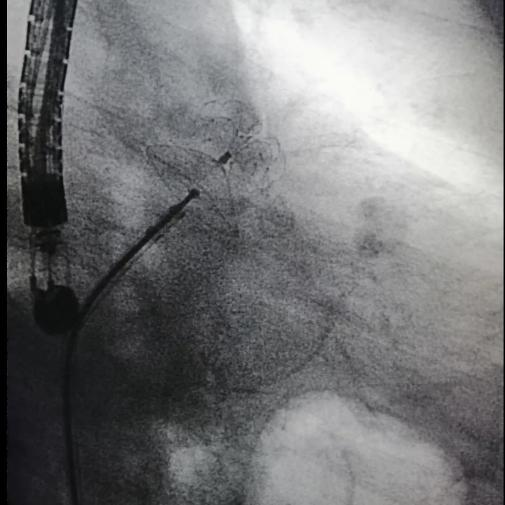

2021年8月28日上午10点,手术正式开始。食管彩超显示左心耳无血栓,李耀东教授带领奎屯医院心内科王飞、杨鸿英、张娟医生进行房间隔穿刺,左心耳造影结果显示为鸡翅型左心耳,在测量左心耳开口宽度和深度后,确定锚定区与封堵区,李教授选择了LAmbre™ 2430封堵器,经输送鞘管送至左心耳实现封堵。造影及食道超声显示均无残余分流,牵拉测试稳定,符合COST原则,释放后取得了理想的封堵效果。随后李耀东教授带领团队对患者4条肺静脉进行冷冻消融,手术历时2小时顺利成功,术后第二日患者活动正常,身体恢复良好。